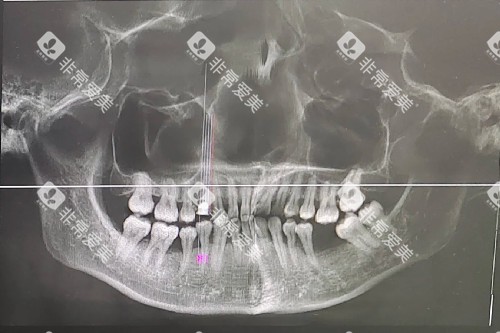

当牙齿开始"跳摇摆舞",说明牙周炎已经进入中晚期!炎症会破坏牙槽骨这个"地基",就像树根失去土壤支撑,牙齿自然会摇摇欲坠。更扎心的是,这个过程不可逆——失去的牙槽骨不会自己长回来!

用指尖轻轻晃动牙齿(别用蛮力!),如果感觉到明显松动,或者用牙签轻戳牙龈边缘有疼痛感,赶紧去看牙医!这时候每拖延一天,就可能多损失0.1毫米的牙槽骨!